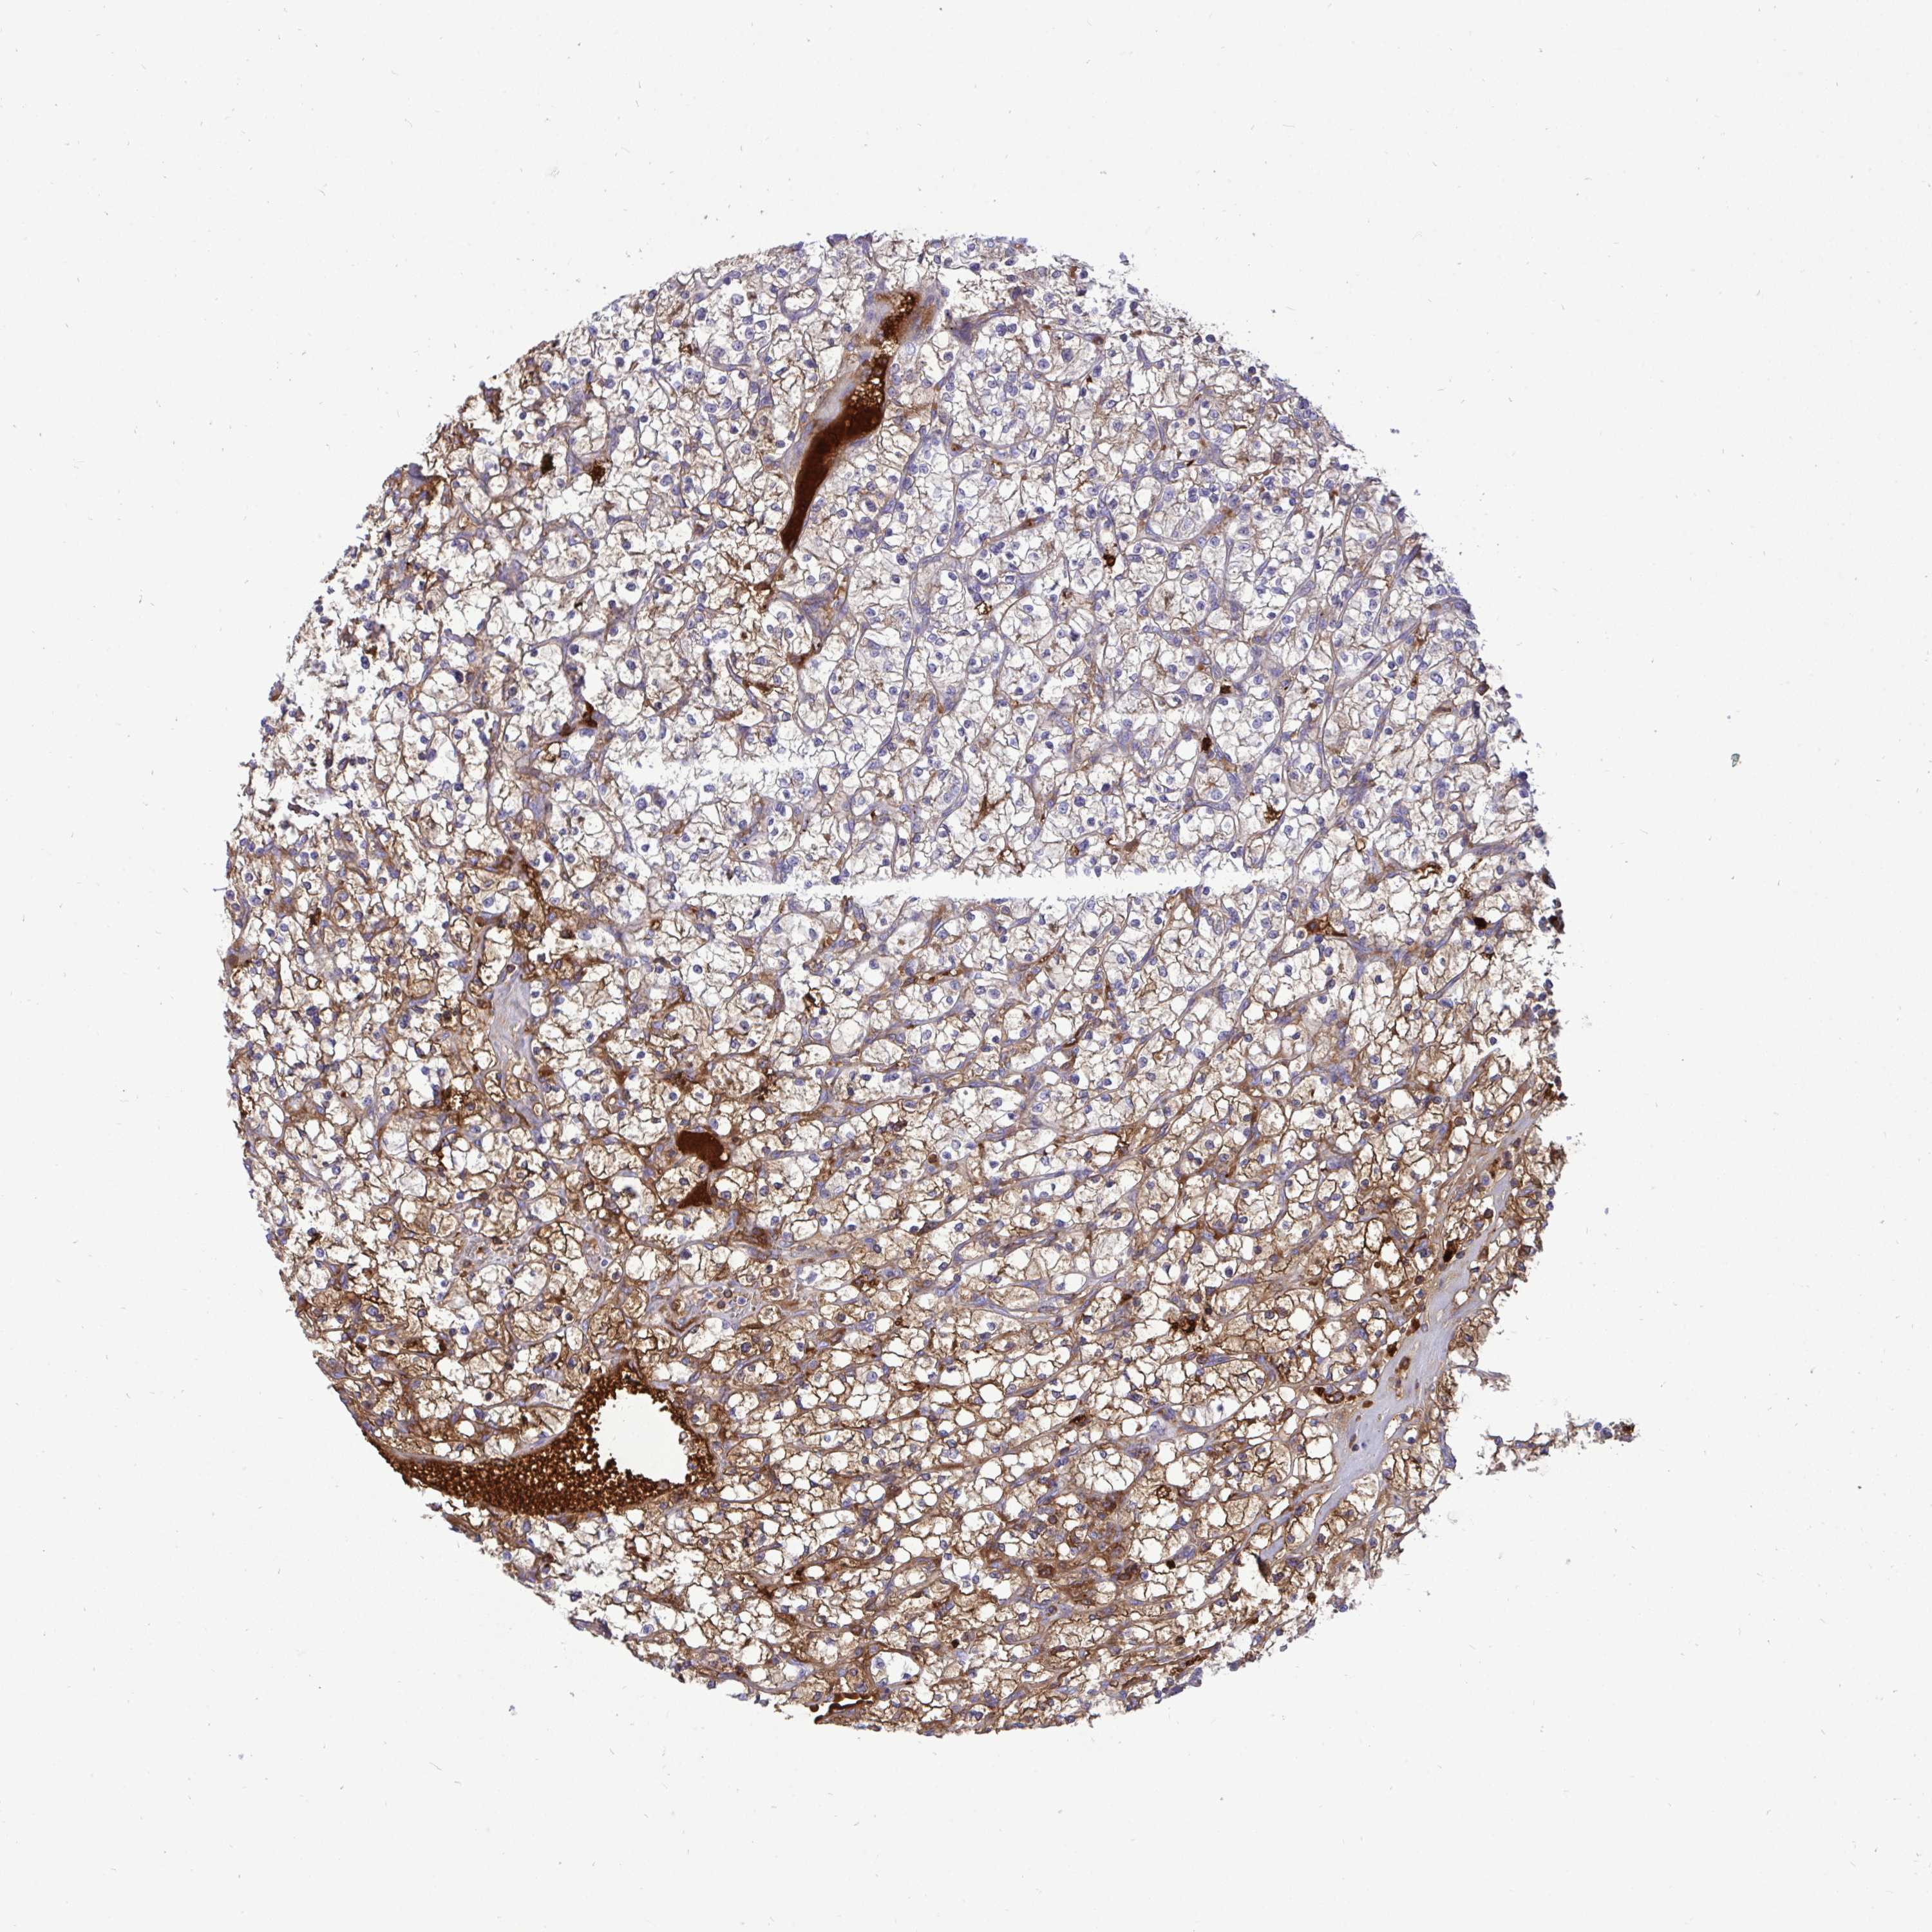

CANCER RENAL CANCER Show tissue menu

KICH TCGA KIRC TCGA KIRC VALIDATION KIRP TCGA PROTEIN RCC CPTAC PROTEIN EXPRESSION

Average pTPM 4.2

Number of samples 521